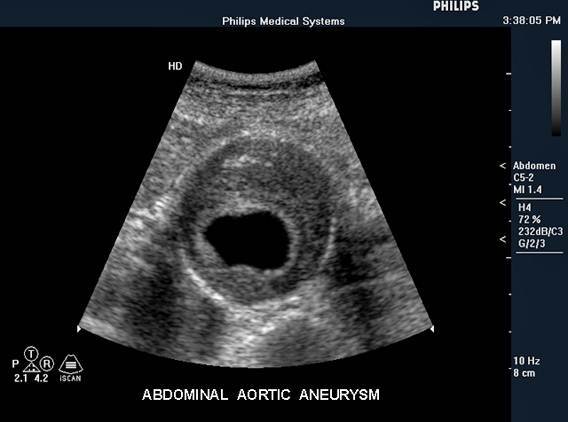

Abdominal Aortic Aneurysm (AAA):

Transverse aortic aneurysm with thrombus